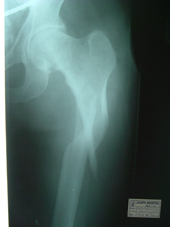

| Fracture neck of femur pre op |

Fracture neck of femur post op |